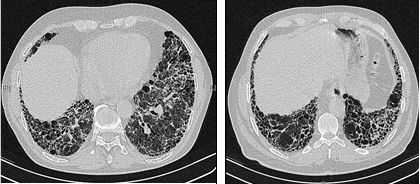

고해상 전산화 단층 촬영(HRCT)은 특발성 폐섬유증 진단에 가장 중요한 검사 방법 중 하나이다. HRCT에서 전형적인 통상적 간질성 폐렴(UIP) 소견, 즉 양쪽 폐 기저부와 흉막 하부에 뚜렷한 벌집 폐 소견을 동반하는 망상 음영과 미세한 유리 음영이 확인되면 수술적 폐 생검 없이 IPF로 진단할 수 있다.[3]

HRCT에서 전형적인 UIP 패턴이 보이지 않는 경우, 확진을 위해 개흉술 또는 흉강경 검사를 통한 외과적 폐 생검이 필요할 수 있다.[3] IPF 환자의 폐 조직은 특징적인 조직 병리학적 UIP 패턴을 보이며, 주요 특징은 '패치워크 패턴'의 간질 섬유증, 간질 흉터, 벌집 변화 및 섬유아세포 초점이다.